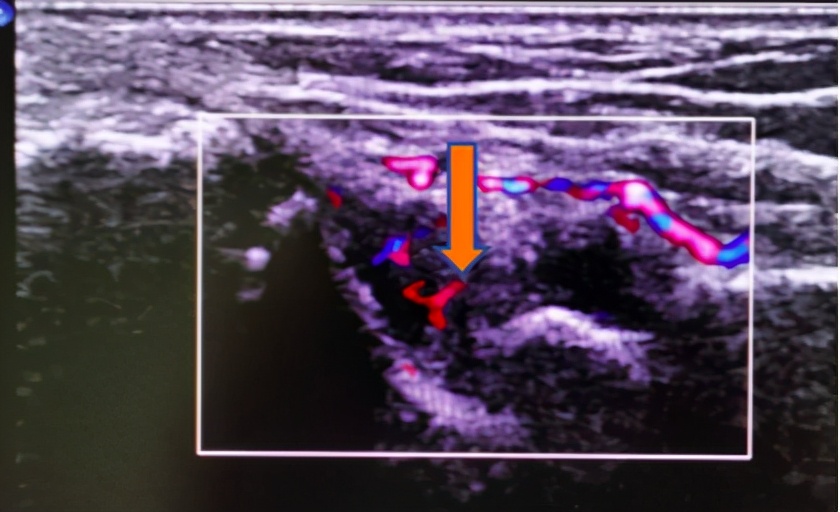

图一为增厚的滑膜组织,内部血供丰富。

经过一番检查,超声发现手、腕部肿痛处存在明显滑膜炎,血流丰富,并且腕骨表面已经出现了侵蚀表现。最终结合化验结果、症状查体及超声检查结果,患者被诊断为 类风湿关节炎 ,给予相应的药物治疗后,肿痛有缓解,但仍有反复,于是再次复查腕关节超声,腕关节背侧滑膜炎较前好转,但仍较严重。胡安鑫副主任医师和其主治医师沟通后,征得患者同意,决定行 超声引导下腕关节注射治疗,直接将药液注射至滑膜炎最严重处 ,不久患者症状便得到了逐渐的缓解。